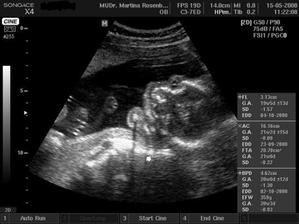

15.5. na kontrole vše v pořádku a asi opravdu budeme holčička, váhu máme 360 g a měříme 16 cm od temene hlavičky po prdelku. Příští kontrola 12.6. a o týden později 3D ultrazvuk...............